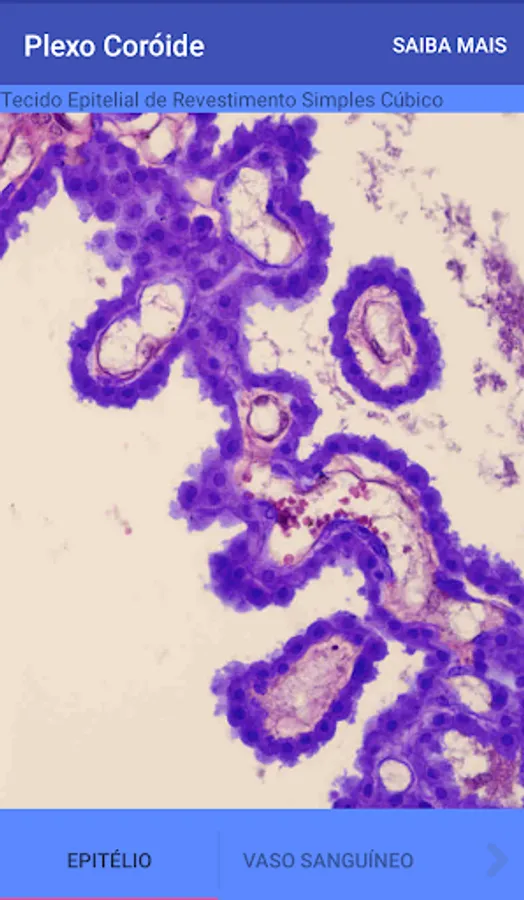

Choroid plexus